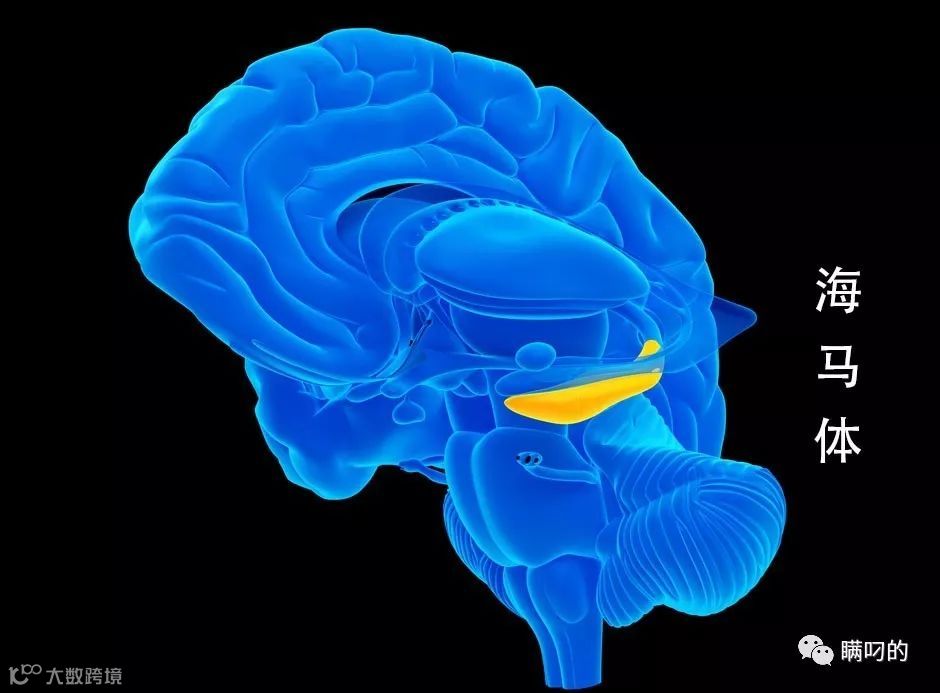

记忆移植就是这个领域研究的重点。现在,美国科学家已经发现大脑海马体的记忆密码,开始尝试用芯片备份记忆,然后把芯片植入另一个大脑,实现记忆移植。这个实验已经在猴子身上取得成功。